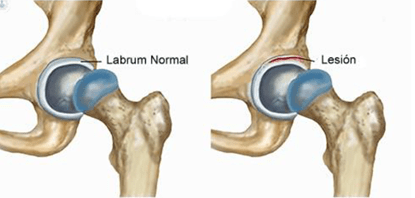

4. Lesión del labrum

El labrum acetabular es un anillo de fibrocartílago que rodea la cavidad de la cadera y ayuda a mantener la cabeza del fémur en su sitio. Puede lesionarse por traumatismos (caídas, deportes de contacto), por movimientos repetitivos en deportes de impacto (fútbol, artes marciales, danza) o por alteraciones estructurales como el pinzamiento femoroacetabular o (FAI).

Los síntomas principales son:

- Dolor profundo en la ingle o en la parte lateral de la cadera, que puede empeorar al estar mucho tiempo sentado, girar o correr.

- Chasquidos, bloqueos o sensación de enganche

- Inestabilidad o pérdida de fuerza.